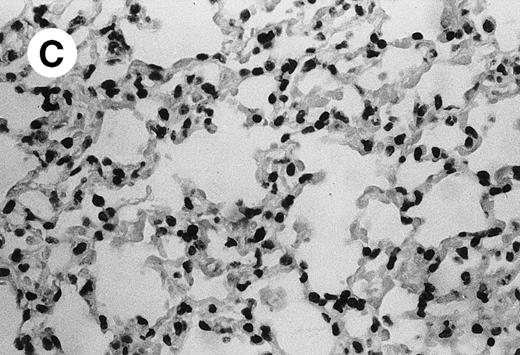

IV injection of MWReg30 caused within 15 minutes a peripheral vasodilatation, as evidenced by red extremities (tail and feet) and uncoordinated movements. These signs persisted for 60 to 90 minutes. Proportional to the injected dose of MWReg30, mice showed intestinal hemorrhages, ruffled fur, and reduced flow rate during blood sampling. Lung, kidney, and liver were sampled at different times after MWReg30 injection for histological examination. Histopathology of the whole lung performed 60 minutes after injection showed enhanced thickness of alveolar septa, due to edema and to increased cellularity, consisting of polymorphonuclear and mononuclear cell accumulation in capillaries, as compared with lungs from mice injected with PBS (Fig 4) or control IgG (not shown). This change was found to be uniform, not focal, in the two lungs (n = 6). After 24 hours, lungs showed a further enhancement of septa thickness, due to mononuclear, but not polymorphonuclear, cell accumulation in capillaries and interstitium, as well as plasma leakage into the alveolar space (Fig 4C). No changes were observed in peribronchiolar areas. As early as 20 minutes after IV injection, semithin sections showed that the vascular engorgement was essentially due to red blood cells, with very few leukocytes or platelets (Fig 4D). Twenty-four hours after injection, some mice showed centrolobular necrosis in the liver as well as glomerular shrinkage and enlargement of Bowman spaces in the kidney, compatible with hemodynamic changes of shock, but without evidence of acute tubular necrosis. Thrombi or microthrombi were not seen in any of the examined organs. Platelets recovered from the blood of mice 30 minutes after injection of MWReg30 did not express P-selectin as determined by FACS analysis. In sera from mice obtained 90 minutes after injection of MWReg30, no TNF was detectable.

Lung histopathology. Aspect of alveolar walls 60 minutes after IV injection of PBS (A) or 10 μg of MWReg30 (B); (C) 24 hours after IV injection of 10 μg of MWReg30; (D) vascular engorgement of septal capillaries with erythrocytes, 20 minutes after IV injection of 100 μg of MWReg30. (A through C) Hematoxylin/eosin staining of paraffin-embedded section (original magnification × 400). (D) Toluidine blue staining of Epoxy resin-embedded sections (original magnification × 1,000).

The lung congestion, as well as the increased cellularity of the lung septa, due to mononuclear and polymorphonuclear cells, are akin to LPS-induced lung pathology. The vascular engorgement, essentially due to erythrocytes, was more pronounced than in mice injected with 1,000 μg LPS (not shown). Histological examination showed that these changes were neither focal nor associated with atelectasis: the increased cellularity was uniform and was observed in both lungs. In contrast, control lungs from mice injected either with PBS or with normal IgG were consistently free of accumulated cells in the septa. In MWReg30-injected animals, the increased cellularity appeared to be due to cell accumulation in both vascular and interstitial compartments, although electron microscopic studies are required to clarify this point. Preliminary studies show enrichment of pinocytotic vesicles (Männel et al, manuscript in preparation). Altogether, the picture is compatible with the very early steps of acute lung injury.